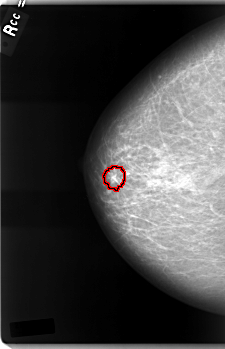

C_0003_1.RIGHT_CC

RIGHT_CC LINES 5928 PIXELS_PER_LINE 3824 BITS_PER_PIXEL 12 RESOLUTION 50 OVERLAY

FILE: C_0003_1.RIGHT_CC.OVERLAY

TOTAL_ABNORMALITIES 1

ABNORMALITY 1

LESION_TYPE MASS SHAPE IRREGULAR MARGINS SPICULATED

ASSESSMENT 5

SUBTLETY 5

PATHOLOGY MALIGNANT

TOTAL_OUTLINES 1

BOUNDARY